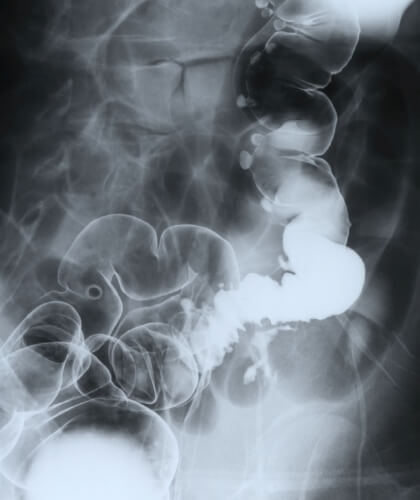

大腸憩室というのは、一部の大腸の壁が外にふくらんで袋のような形になる病態です(図4)。治療が必要になるケースは多くないのですが、時として、そこで炎症(憩室炎)が生じて穿孔(孔があくこと)、出血や狭窄(腸が狭くなること)、が生じた場合は、手術などの治療が必要になります。大腸憩室炎に対する腹腔鏡手術は難度が高く、開腹アプローチが一般的ですが、当科では憩室炎に対し積極的にこのような低侵襲手術(患者さんに優しい手術)を行っています。(最近8年間で77例)また、比較的まれですが、憩室炎は結腸膀胱ろう(大腸と膀胱に蟻の巣のようなトンネルができて、尿に便やおならが混入する病態)に進展して治療に難渋することがあります。このような患者さんの手術も最近6年で9例の経験あり、すべて腹腔鏡手術で完治しています。

図4 憩室症